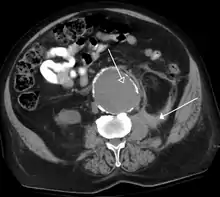

The most common technique is to perform portal venous phase imaging in the abdomen and pelvis (approximately 60–90 seconds after contrast administration, figure 2). This results in near optimal contrast opacification of the majority of the solid abdominal organs and it is used for a wide variety of indications: nonspecific abdominal pain; hernia; infection; masses (with a few exceptions such as hypervascular, renal, and some hepatic tumors); and in most follow-up examinations. As a general rule, this single phase is adequate unless there is a specific clinical indication that has been shown to benefit from other phases.

FIGURE 2. Contrast enhanced CT demonstrating parenchymal enhancement of the intra-abdominal organs in the portal venous phase (axial left, coronal reformat right).